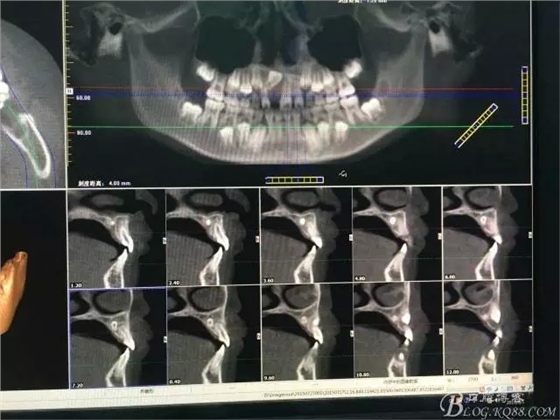

圖1.術(shù)前CBCT檢查:11牙冠90°唇側(cè)傾斜,21和22根尖區(qū)腭側(cè)有一埋伏多生牙